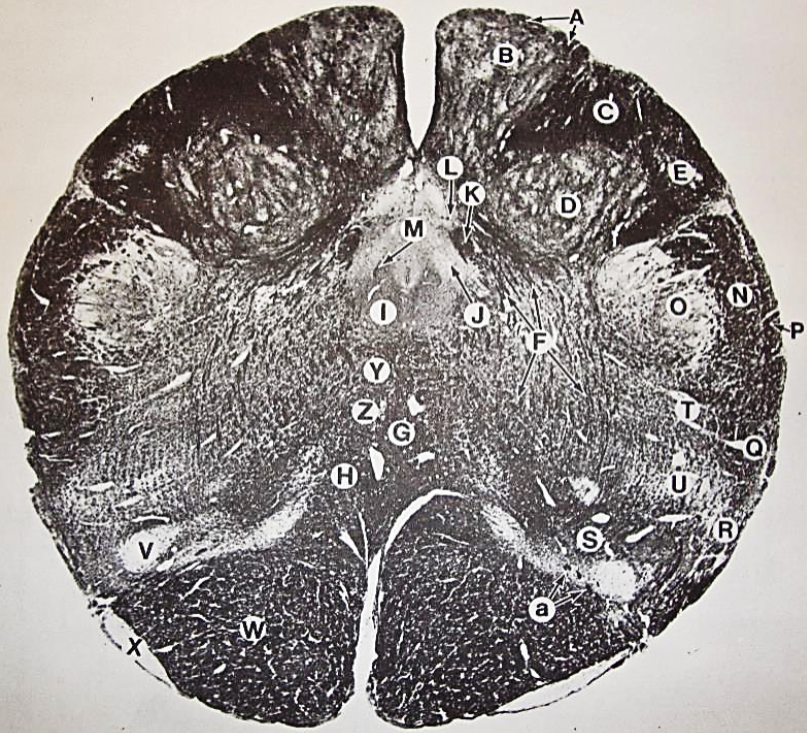

A

Fasciculus gracilis

B

gracile nucleus

C

fasciculus cuneatus

D

cuneate nucleus

E

spinal trigeminal tract

F+G collectively

spinal trigeminal nucleus

H

accessory nucleus

I

pyramidal decussation

J

rubrospinal tract

K

posterior spinocerebellar tract

L

anterior spinocerebellar tract

M

lateral spinothalamic tract

N

anterior spinothalamic tract

O

lateral vestibulospinal tract

P

medial longitudinal fasciculus

Q

tectospinal tract